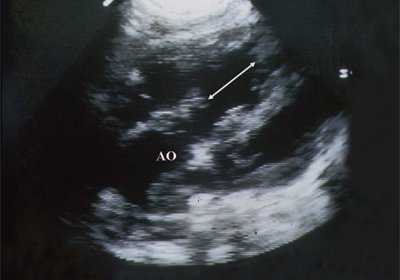

В равной степени это относится к дефекту межжелудочковой перегородки (рис. 6), простой форме транспозиции магистральных сосудов (рис. 7, 8), транспозиции магистральных сосудов с дефектом межжелудочковой перегородки (синдром Тауссиг - Бинга) (рис. 9), общему желудочку (рис. 10), общему артериальному стволу (рис. 10), двойному отхождению сосудов от одного из желудочков сердца (рис. 11).

Рис. 9. Синдром Тауссиг - Бинга. Легочная артерия (отмечена стрелкой) расположена над дефектом межжелудочковой перегородки.

Рис. 10. Общий желудочек с отхождением TRUNCUS ARTERIOSUS. Стрелками показано разделение TRUNCUS ARTERIOSUS на аорту и ствол легочной артерии.

Рис. 11. Двойное отхождение магистральных сосудов от левого желудочка. Длинная ось сердца. Магистральные сосуды инвертированы и отходят от левого желудочка. Аорта расположена "верхом" над дефектом межжелудочковой перегородки (стрелка).

LV и RV - левый и правый желудочек, АР - легочная артерия, АО - аорта, VSD - дефект межжелудочковой перегородки.